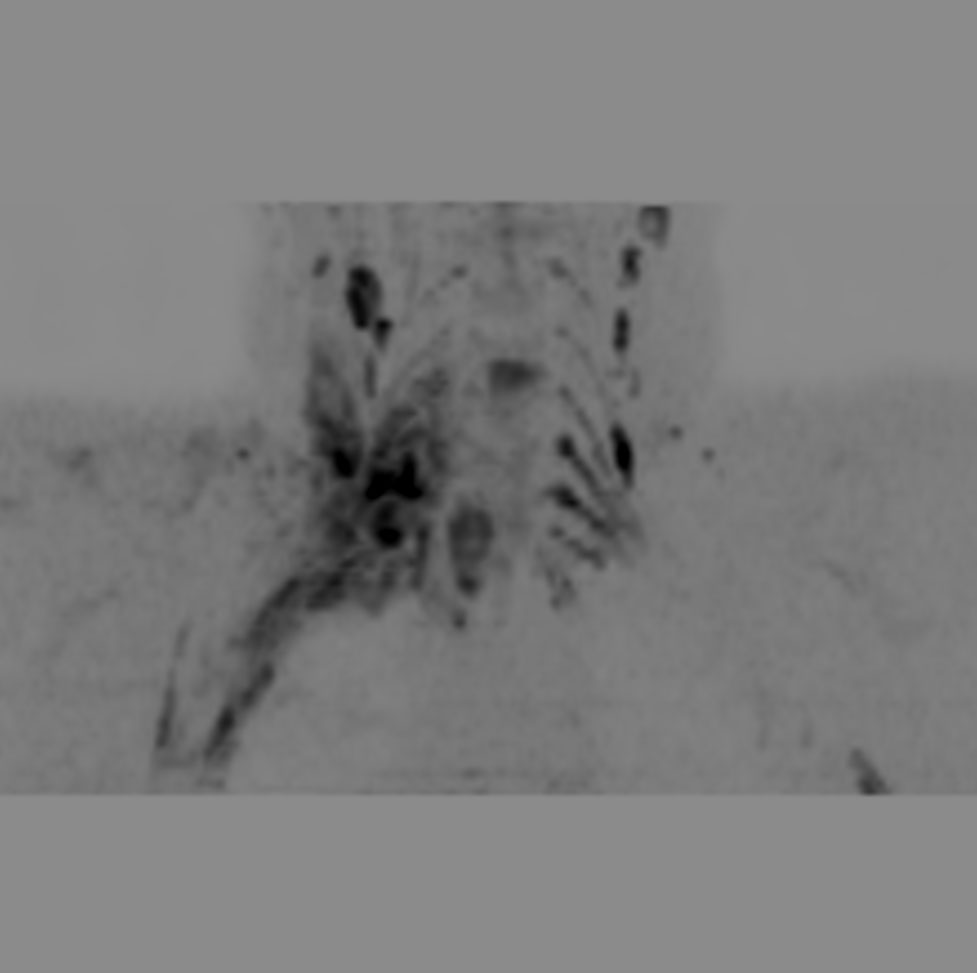

Coronal DWIBS (MIP)

Axial DWIBS (MIP)